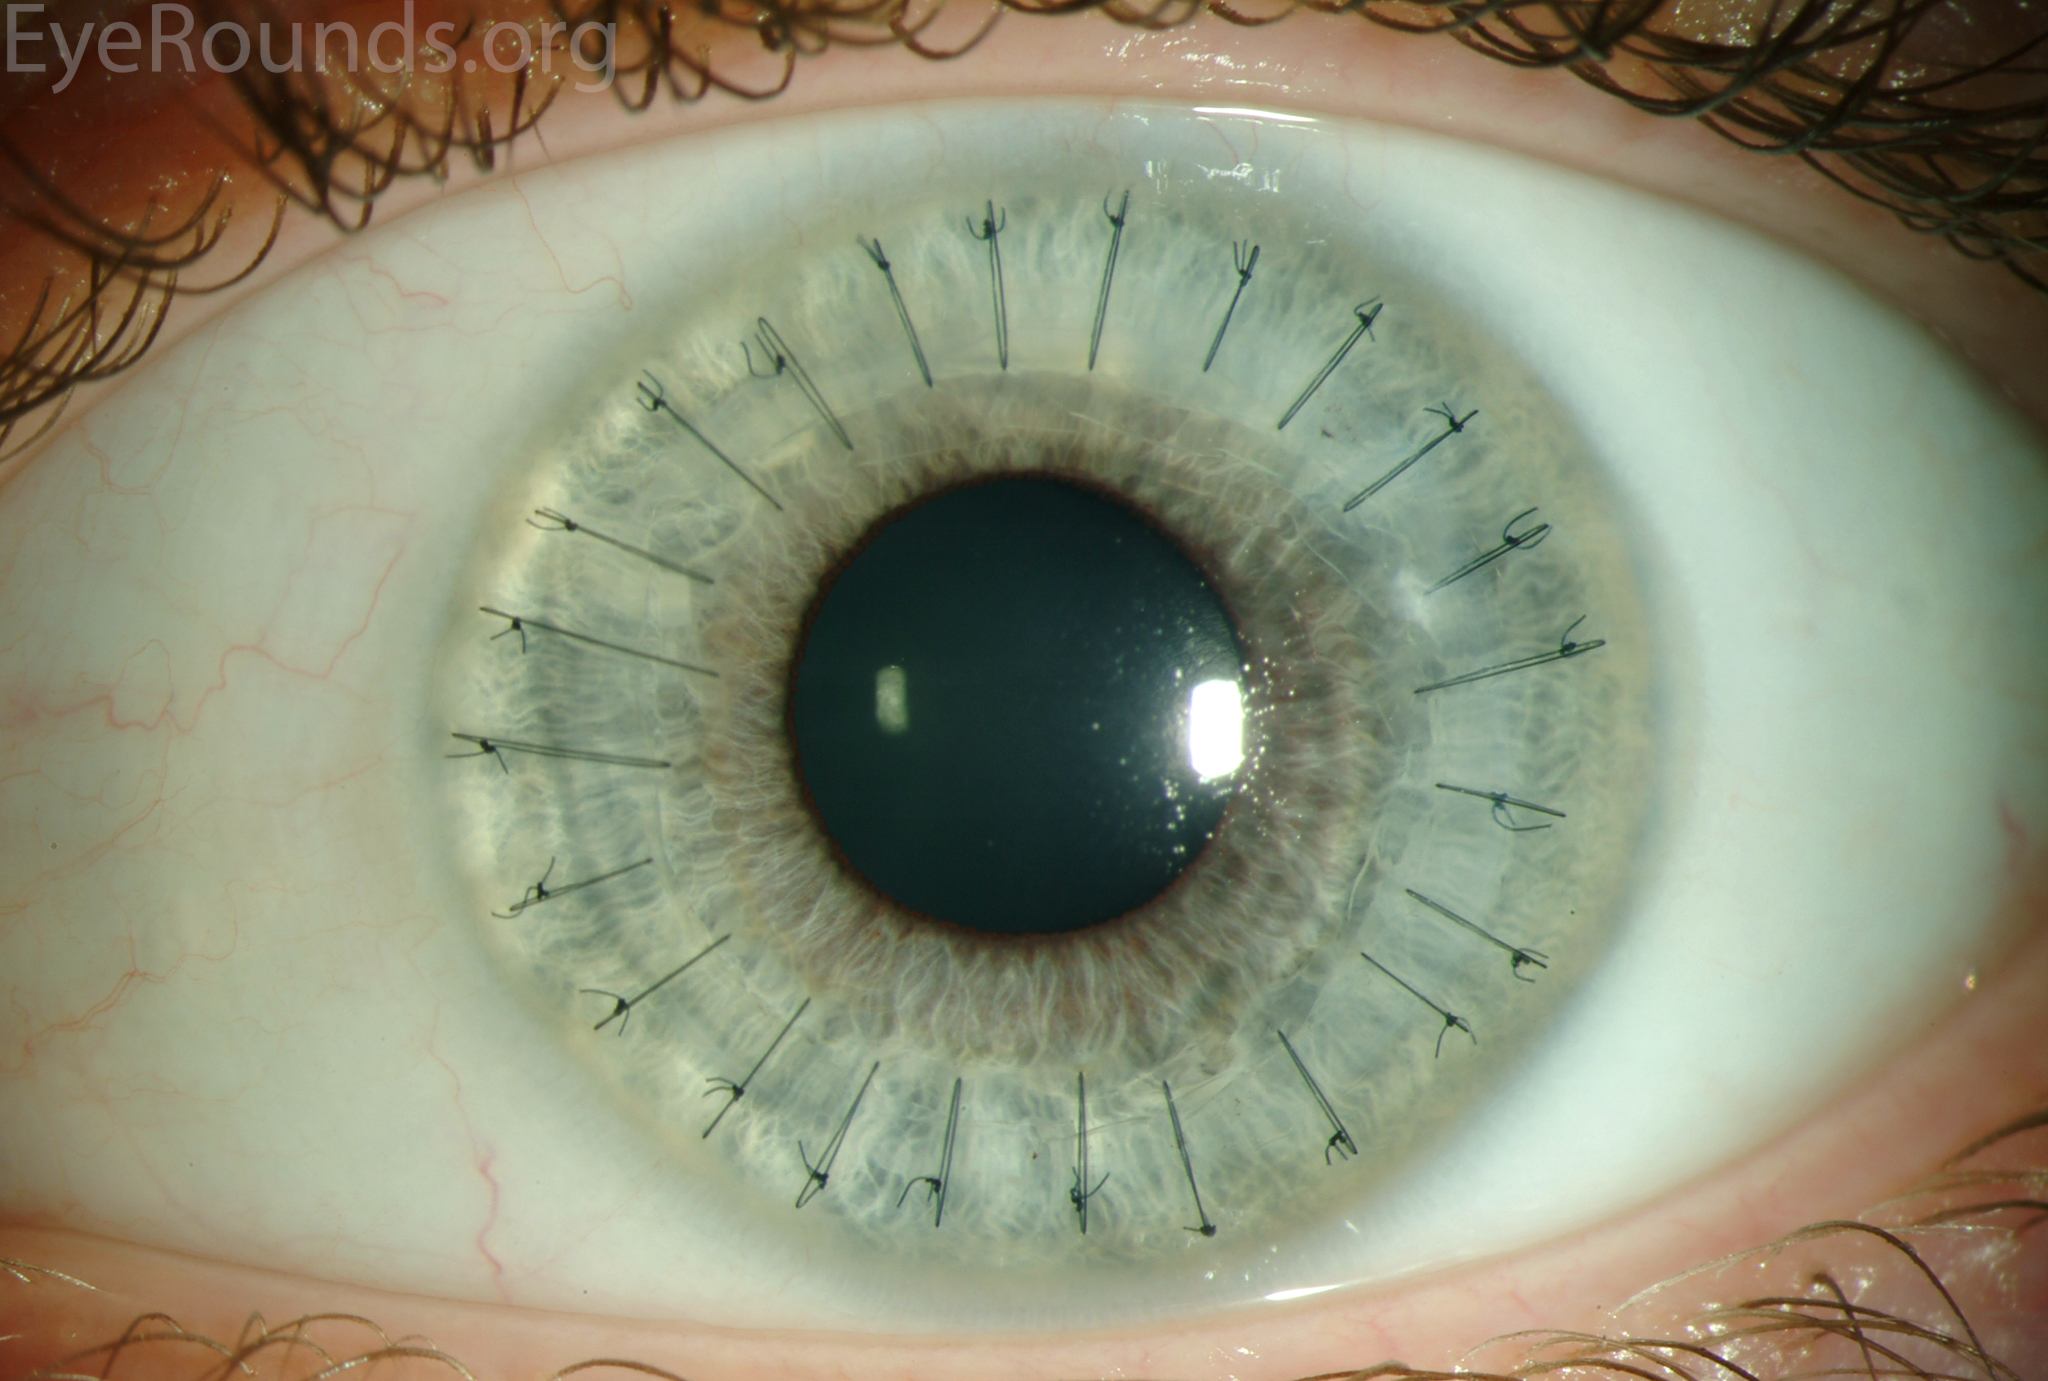

PK is a full-thickness transplant procedure, in which a trephine of an appropriate diameter is used to make a full-thickness resection of the patient's cornea, followed by placement of a full-thickness donor corneal graft. Interrupted and/or running sutures are placed in radial fashion at equal tension to minimize post-operative astigmatism (Figure 2). Later, the sutures are removed selectively to reduce the amount of astigmatism present. A transplant can last decades with proper care (Figure 3). While once the most prominent type of corneal transplant, PK has been supplanted by partial thickness techniques for endothelial dysfunction without significant stromal scarring. PKs are performed primarily for visually significant stromal scarring, opacities with an uncertain status of the endothelium or significant posterior corneal involvement, corneal ectasia (such as keratoconus and pellucid marginal degeneration, especially if there is history of hydrops), combined stromal and epithelial disease (such as Peters anomaly), and infectious or non-infectious corneal ulcerations or perforations (1, 14). A variant of the procedure, the mini-PK, can be used to treat more focal defects in the cornea (Figure 4).